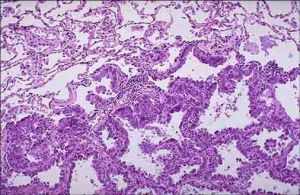

(四)腺癌

腺癌包括眼泡狀、乳頭狀、細支氣管-肺泡癌和實體瘤伴粘液形成。女性多見,災難性亦有增多趨勢。與吸菸關係不大,多生長在肺邊緣小支氣管的粘液腺,因此在周圍型肺癌中以腺癌為最常見。腺癌約占原發性肺癌25%。腺癌傾向於管外生長,但也可循泡壁蔓延,常在肺邊緣部形成直徑2-4cm的腫塊。腺癌富血管,故局部浸潤和血行轉移較鱗癌早。易轉移至肝、腦和骨,更易累及胸膜而引起胸腔積液。

典型的腺癌細胞,呈腺體或乳頭狀結構,細胞大小比較一致,圓形或橢圓形,胞漿豐富,常含有粘液,核大,染色深,常有核仁,核膜比較清楚。